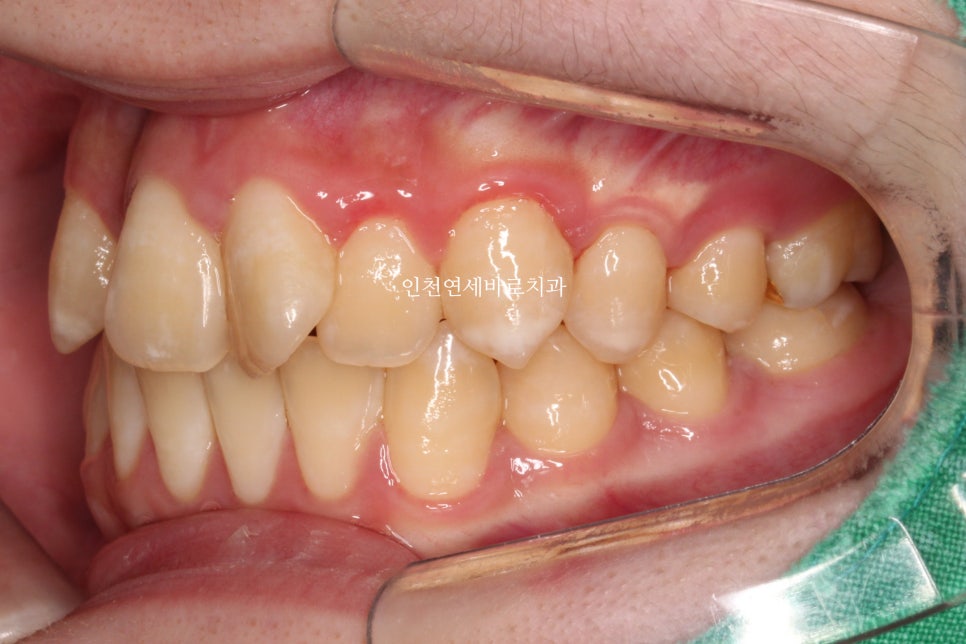

위와 같이 삐뚤삐뚤했던 치열을 가진 아이가 와서 #철사교정 치료를 하고

마무리가 되었습니다.

스마일이 훨씬 자연스러워져 보입니다.